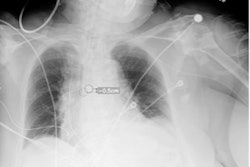

Example of an acceptable AI–generated chest x-ray report. (A) Anteroposterior chest x-ray in a 68-year-old female patient who visited the emergency department because of acute-onset dyspnea shows an enlarged heart, bilateral pleural effusion, and bilateral interstitial thickening, suggesting heart failure and interstitial pulmonary edema. (B) The AI-generated report appropriately describes the findings of the x-ray and suggests a possible diagnosis. All seven thoracic radiologists evaluated the AI-generated report as acceptable without revision.RSNA